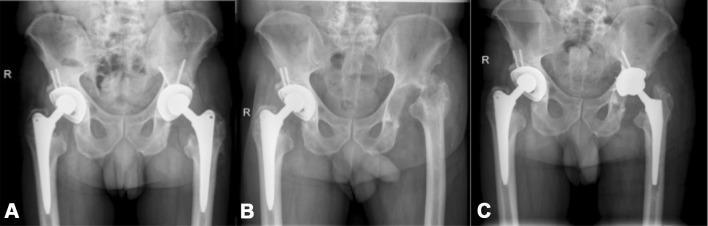

The aim of this study was the evaluation of possible outcome differences of patients undergoing two-stage hip exchange with antibiotic-loaded spacers, compared to patients without an interim spacer implantation.

We evaluated 46 patients undergoing two-stage hip revision surgery. Twenty-five patients received an interim ALS. Additional to a Kaplan-Meier survival analysis, a competing risk analysis was performed to estimate the cumulative incidence function for re-revisions due to infection accounting for death as a competing event.

Nine patients (seven non-ALS vs. two ALS) had to undergo re-revision surgery due to reinfection of the hip joint. The non-ALS group showed a risk of re-revision of 19% (95% CI 5-38%) at 12 and 24 months and 30% (95% CI 12-51%) at 36 months. The group with ALS implantation displayed a 0% risk of re-revision surgery in the first 36 months. The Gray test revealed a significant difference in the cumulative incidence between both observed groups (p = 0.026).

Our findings suggest that ALS implantation significantly reduces the risk of reinfection after two-stage hip revision surgery.